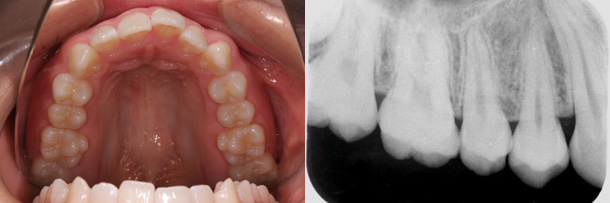

症例1:叢生

主訴:歯並びを治したい

年齢:20歳

診断:上下顎叢生・上顎骨幅径の狭小

装置:上顎急速拡大装置・上下顎ブラケット装置

治療期間:2年5ヶ月(来院回数29回)

抜歯:左右上下顎小臼歯の4本

費用:750,000円+税

矯正前

矯正後